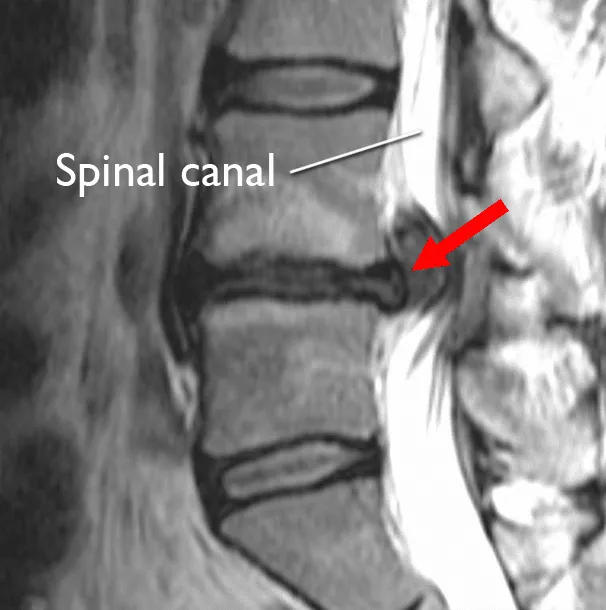

Image: MRI of a herniated disc in the lower back.

Spinal Stenosis

A large disc abnormality, often combined with age-related changes like bone spurs, can narrow the space available for the spinal cord or nerve roots.

- Central canal stenosis: Narrowing of the main spinal canal, which can impact the spinal cord itself.

- Foraminal stenosis: Narrowing of the small opening (foramen) where the nerve root exits the spine.

Measuring the stenosis: The MRI allows providers to accurately measure the remaining cross-sectional area of the spinal canal. This measurement helps determine the functional impact of the disc on the patient’s mobility, especially when standing or walking, and guides the treatment plan toward decompression if necessary.